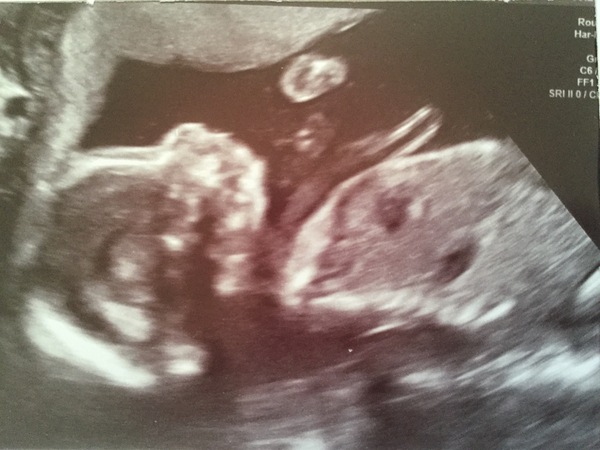

Yay to all these wonderful scans!! It's so exciting isn't it and such a relief to see our little wrigglers